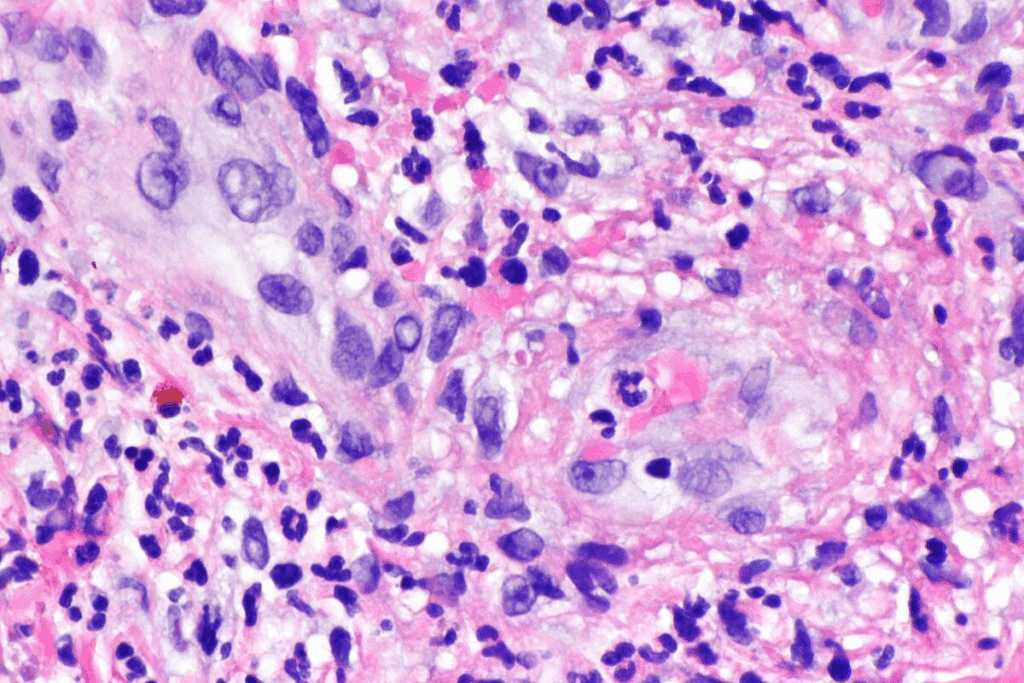

Pathophysiology: How Vasculitis Affects the Skin

Vasculitis is a condition that causes inflammation in blood vessels. This inflammation can lead to different skin problems. It’s important to understand how it affects the skin.

Inflammation Process in Blood Vessels

In vasculitis, immune cells get into the blood vessel walls. This damage causes the skin symptoms we see.

Immune System Involvement

The immune system is key in vasculitis. It sees the blood vessels as foreign and attacks them.

This attack causes inflammation and damage. Knowing how the immune system works helps us find better treatments.